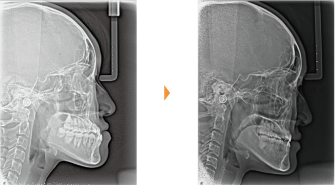

| 主訴 | 前歯の隙間が気になる |

| 年齢・性別 | 42歳 / 女性 |

| 治療方針 | 咬合力により上顎前歯が前方に傾斜したと思われるケース。元に戻りやすいため過蓋咬合をしっかり治して、保定には固定式のリテーナーも併用する。 |

| 抜歯部位 | 非抜歯 |

| 使用装置 | マルチブラケット装置 |

| 治療期間 | 16か月 |

| リテーナー | 上顎インビジブル、フィックス、下顎インビジブル |

| 費用 | 765,000円(税別) |